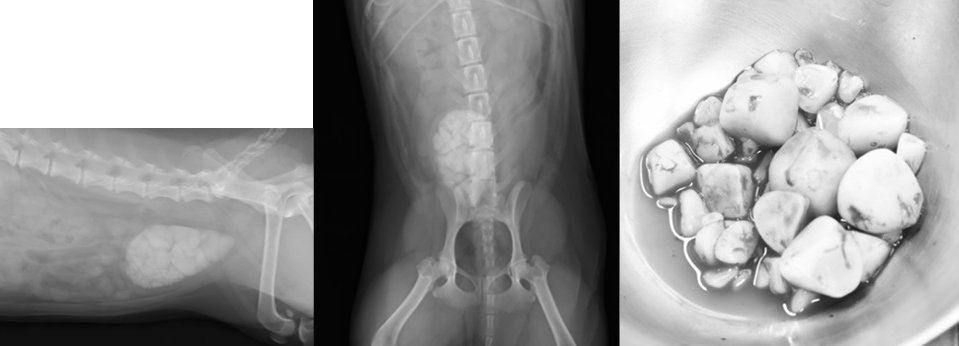

膀胱結石について

膀胱結石とはミネラル成分が固まってできた結石で、尿路結石症の一つです。犬・猫ともに起こり、様々な症状を引き起こします。

全身麻酔下でお腹に小切開(1cmほどを2ヶ所)を行い、膀胱鏡を用いて結石を摘出する方法です。大きめの結石や結石が多数ある場合に用います。カメラを用いるため、結石の取り残しは少なくなります。

開腹下膀胱結石摘出 侵襲度:高